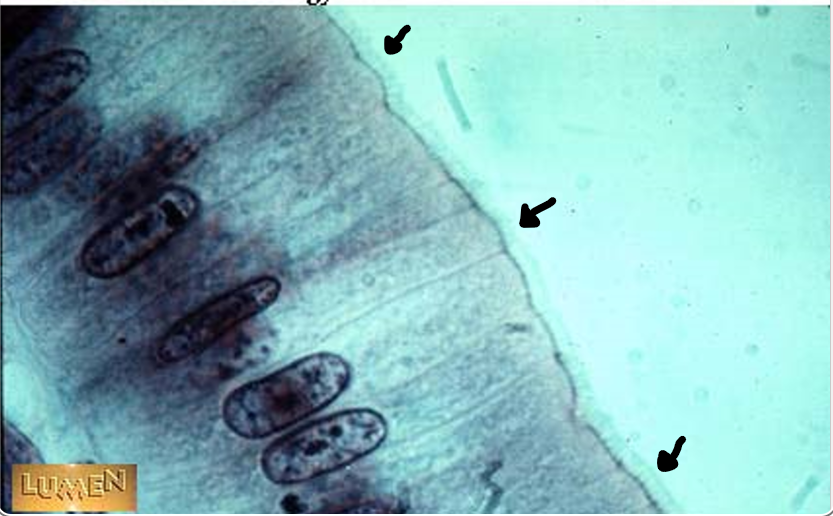

the arrows point to

brush border/microvilli

villi